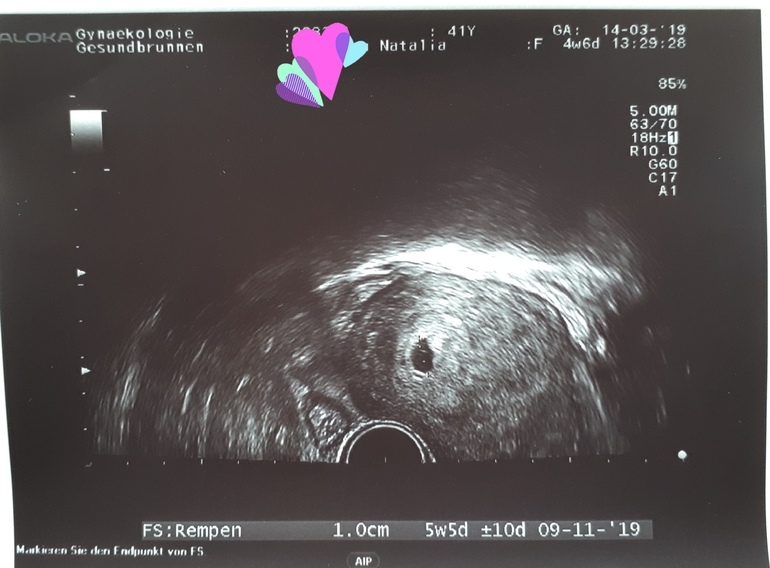

Акушерский срок 4 недели и 6 дней

И уже надо было к Г ехать. Там узи и ПЯ выросло за 3 дня больше чем в 2 раза, с 3,9мм до 10мм. Но эмбрион еще не виден. Следующее узи 27 марта. Для "сравнения" с ЗБ на 4+0 ПЯ 2,1мм, на 5+1 4,4мм.